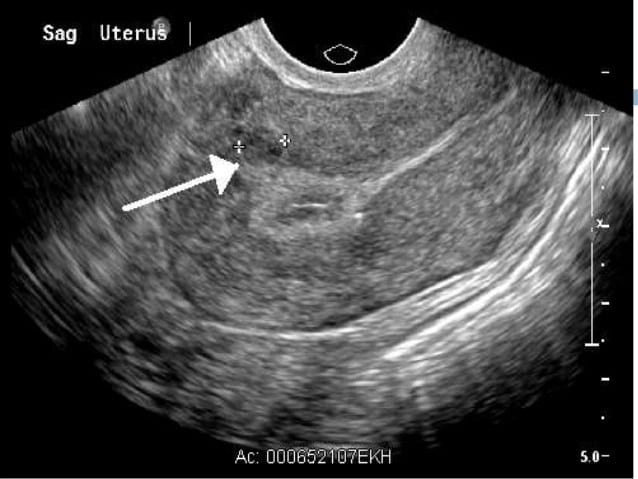

تشخیص معمولاً با شرححال و معاینه لگنی شروع میشود؛ پزشک ممکن است در معاینه به بزرگ شدن یا نامنظمی شکل رحم شک کند. رایجترین آزمون تصویربرداری برای تأیید فیبروم، سونوگرافی لگن است که میتواند از روی شکم یا بهصورت واژینال انجام شود. در صورت نیاز، روشهایی مثل هیستروسکوپی (برای دیدن حفره رحم و بررسی فیبرومهای زیرمخاطی) یا گاهی روشهای تکمیلی دیگر به کار میآید و در برخی موارد نمونهبرداری نیز ممکن است انجام شود.